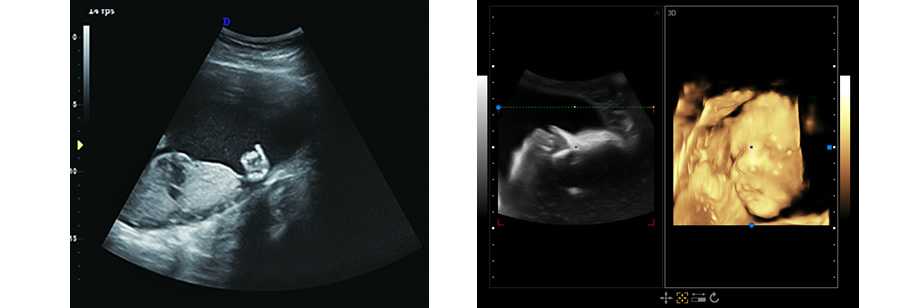

4.支持多種探頭:腹部、心臟、小器官、腔體探頭、直腸探頭、容積探頭

立體光源成像 胎兒容貌實時顯示